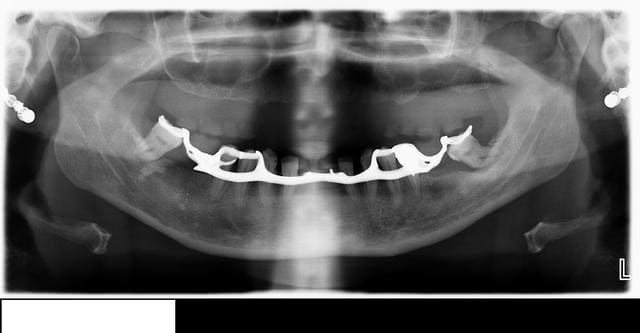

Voici le cas en image

Mon doute portait donc sur la face vestibulaire de l'implant en place de 43.

Implant4.5*11 Astra

Excusez moi pour la pano avec le stellite.